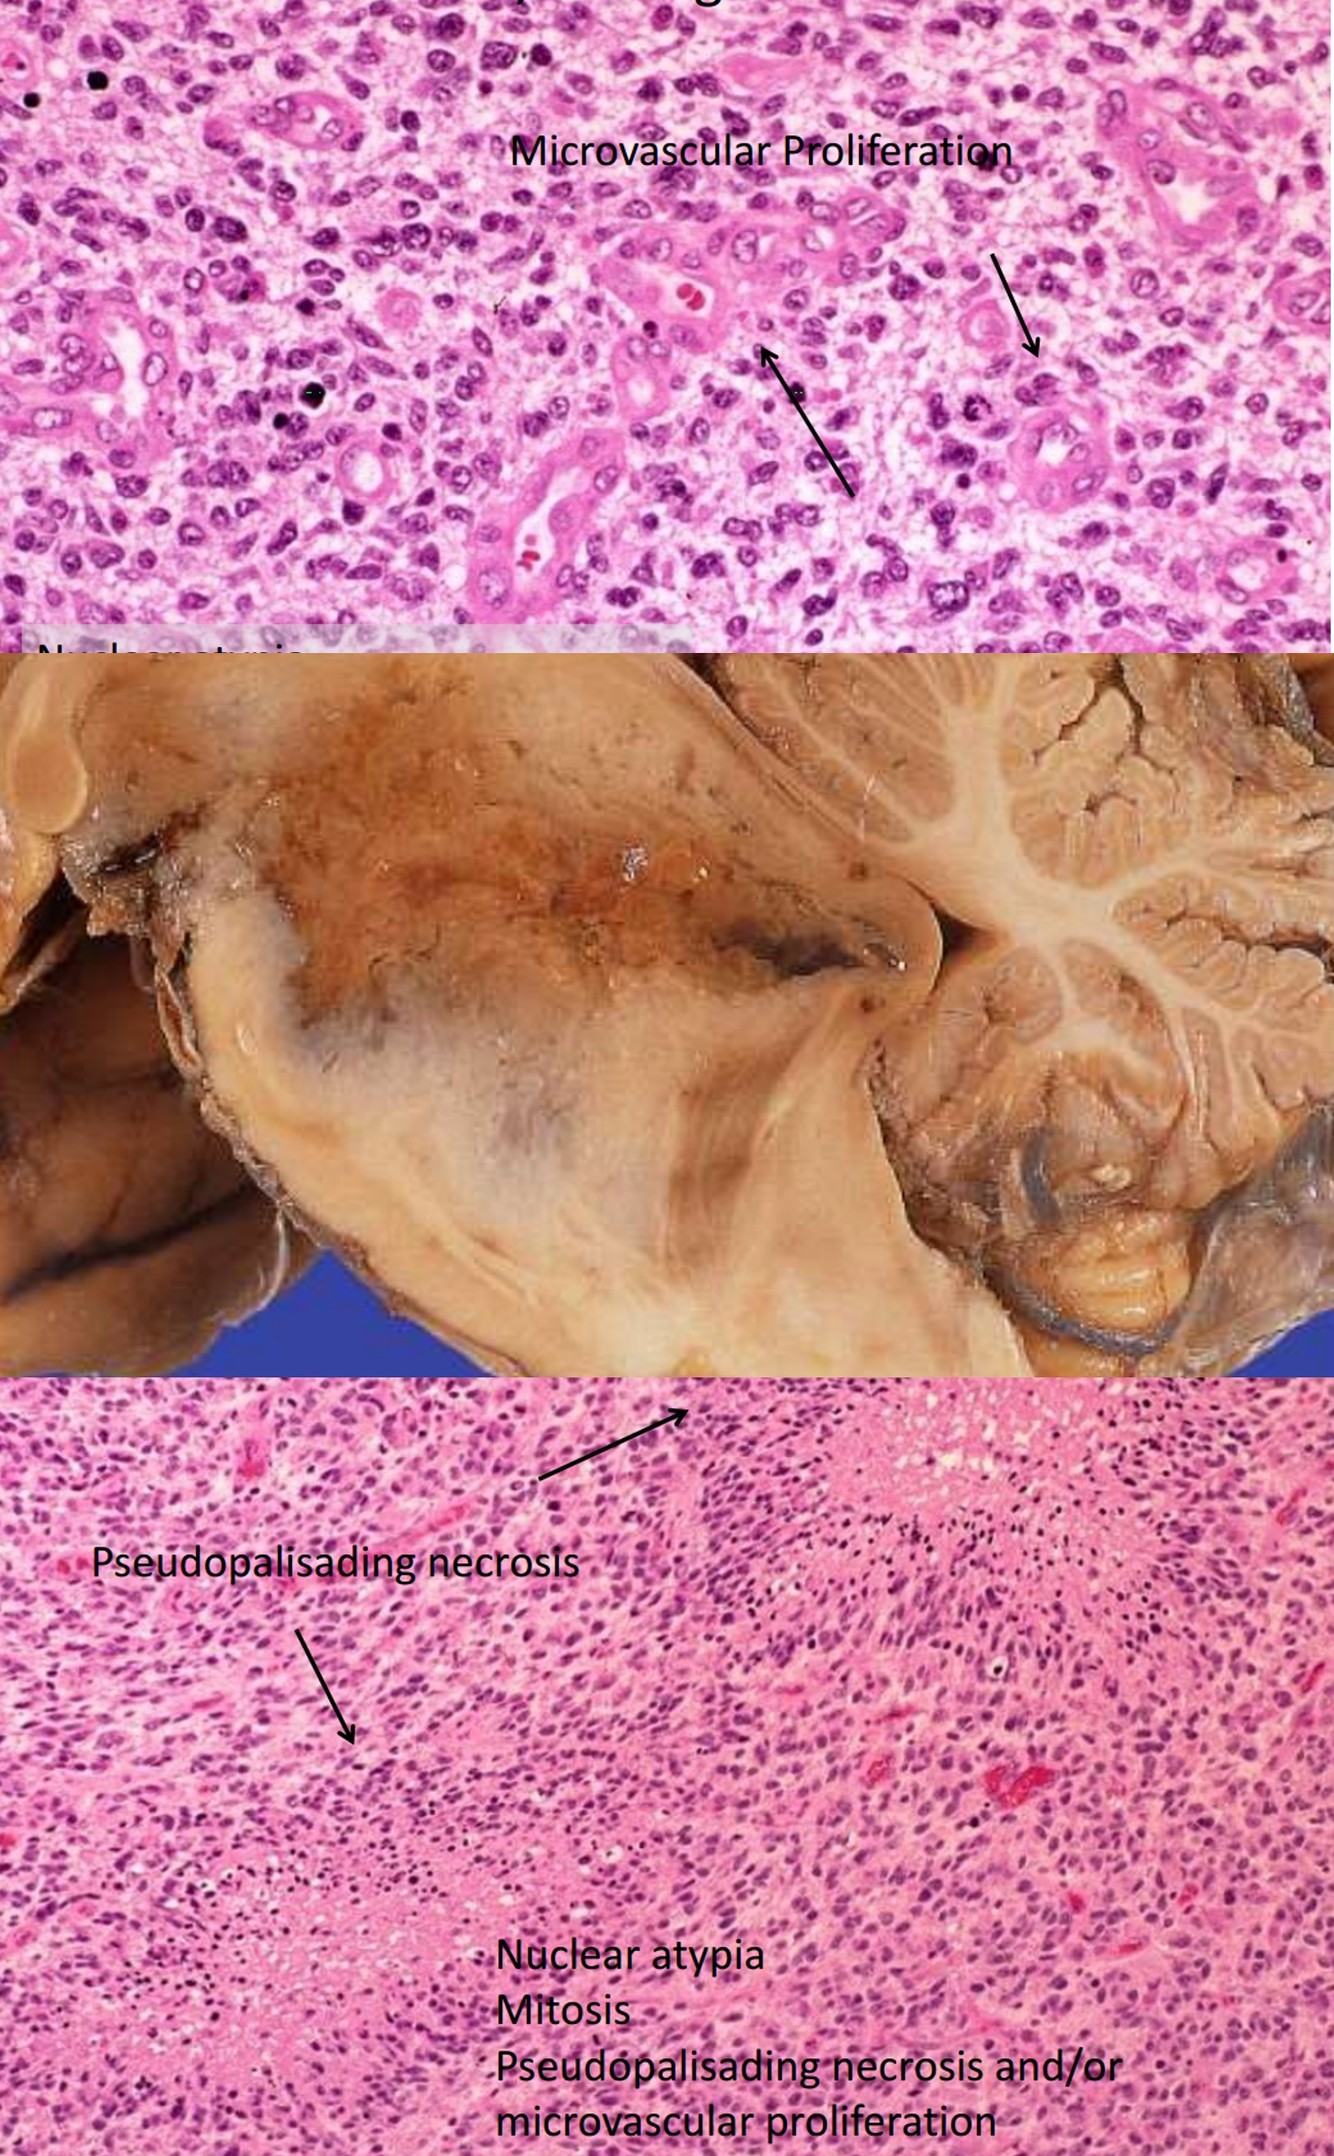

Glioblastoma, WHO grade IV